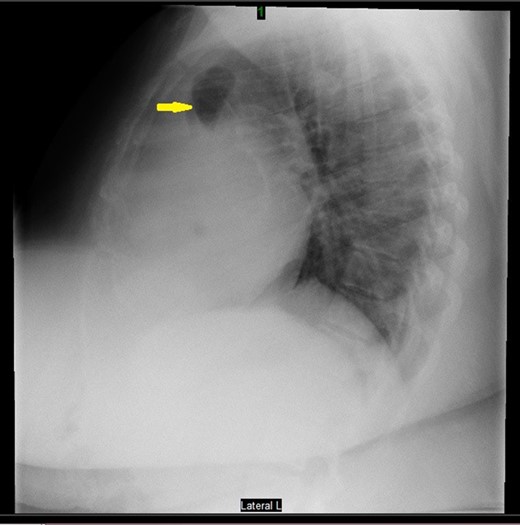

Prior to the surgery patient had symptoms of mild dyspnea, vague abdominal discomfort and an initial evaluation with Chest X Ray revealed bowel gas pattern in the right hemithorax (Fig. 1). A subsequent CAT scan thorax and abdomen revealed a right-sided large morgagni diaphragmatic hernia containing omentum and portion of the transverse colon (Fig. 2). Patient elected to undergo Laparoscopic sleeve gastrectomy and concomitant morgagni diaphragmatic hernia repair. Abdomen was explored laparoscopically which revealed a right sided morgagni diaphragmatic hernia with defect size about 8 × 4 cm, containing omentum, transverse colon and part of the falciform ligament. Contents were reduced successfully taking care not to injure the bowel, falciform ligament partially dissected. A sleeve gastrectomy done. Then the hernial defect was closed primarily by interrupted non absorbable sutures. The closure was then reinforced with a sublay ventralight mesh which was secured using transfascial fixation sutures and with tackers (Fig. 3). The post operative course was unremarkable and the patient was discharged on post operative Day 2 with normal chest X-ray (Fig. 4). At 2 months after surgery the patient was doing well and tolerating solid and liquid diet and no more dyspnea nor GI symptoms.

Laparoscopic sleeve gastrectomy with concomitant Morgagni hernia repair.